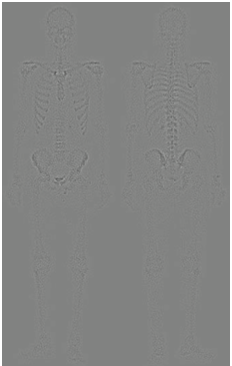

다른 방법은 어떤 방법이 있을 까요? 그 방법은 영상 그래디언트의 스무딩된 버전의 마스크를 사용하는 것입니다. 이러한 과정을 가능한 이유는 미분의 특성에 기인합니다. 라플라시안 필터는 애초에 2차 미분 연산입니다. 따라서 세세한 디테일 개선에는 좋은 결과를 얻을 수 있습니다. 하지만 노이즈가 많은 입력 영상을 받으면 출력 영상 역시 노이즈가 많게 됩니다. 하지만 로버츠나 소벨 연산과 같은 1차 미분 연산자는 라플라시안 필터에 비해서 노이즈나 미세한 디테일에 적은 반응을 보이고, 노이즈나 미세한 디테일을 얻는다고 해도 스무딩을 통해 제거 가능합니다. 따라서, 그래디언트 기반의 필터링을 통해서 엣지를 추출한 뒤 혹시나 남아있는 노이즈를 제거하기 위해 스무딩을 적용하는 것을 샤프닝된 영상의 입장에서는 골격의 마스크로 볼 수 있기 때문에 두 영상을 곱한 결과를 사용하는 것이 합리적입니다. 이를 위해서 위의 사진과 같이 입력 영상에 소벨 연산을 적용하게 됩니다.